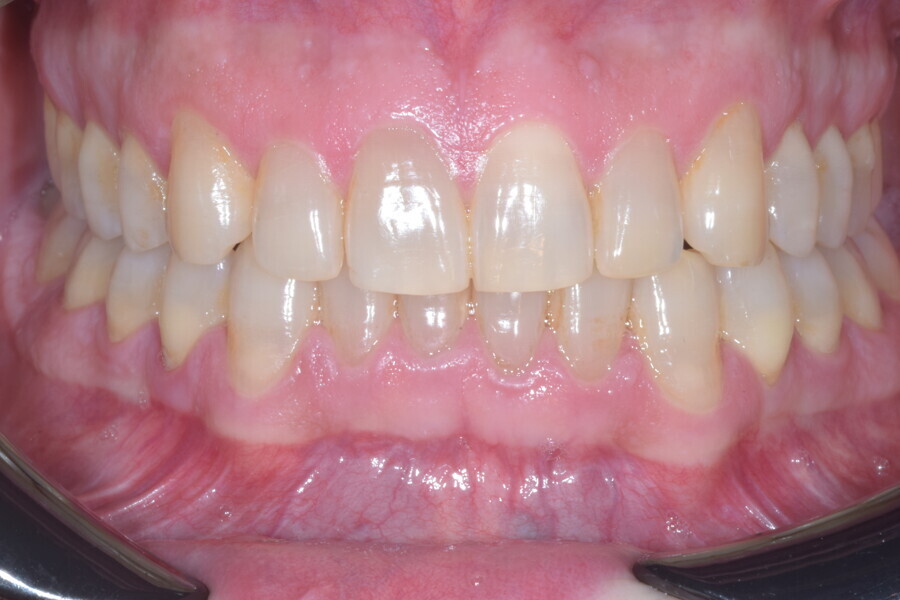

À la fin du traitement, on pouvait observer une relation de classe I des canines et des molaires, une légère augmentation de l’inclinaison des incisives supérieures (Ui-FH = 112°), une correction complète de l’inclinaison des incisives inférieures (IMPA = 97,09°) grâce à la vestibulo-version, et une légère amélioration de l’hypodivergence (SN-GoGn = 27°) résultant de l’extrusion relative des dents postérieures, et de l’utilisation d’élastiques de classe II — petite variation (1°) très intéressante compte tenu de l’âge du patient (Figs. 25–35). La ligne du sourire était harmonieuse et correspondait à une relation idéale entre les incisives supérieures et la lèvre inférieure. Le sourire avait été élargi grâce au contrôle du torque des segments latéraux et postérieurs.

La ligne du sourire était harmonieuse et correspondait à une relation idéale entre les incisives supérieures et la lèvre inférieure. Le sourire avait été élargi grâce au contrôle du torque des segments latéraux et postérieurs. La superposition des tracés céphalométriques montrait des changements intéressants induits par le traitement orthodontique (Figs. 36 et 37) :

Lors du suivi à un an, alors que le patient portait un appareil de rétention (appareil de rétention Vivera avec rampes d’occlusion, Align Technology), le résultat était stable et l’intercuspation était nettement meilleure (Figs. 38–42).